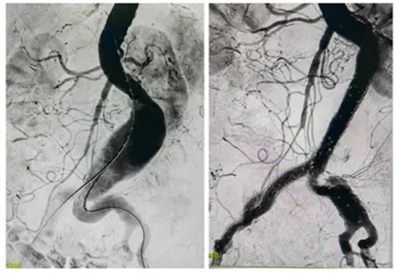

▲ 术中造影,腹主动脉局部瘤样扩张,行“覆膜支架隔绝”封堵良好

这是一种微创手术,仅用2小时就成功拆除了这颗“炸弹”。术后第3天,刘奶奶就能下地自如活动,腹痛也消失了,顺利康复出院。